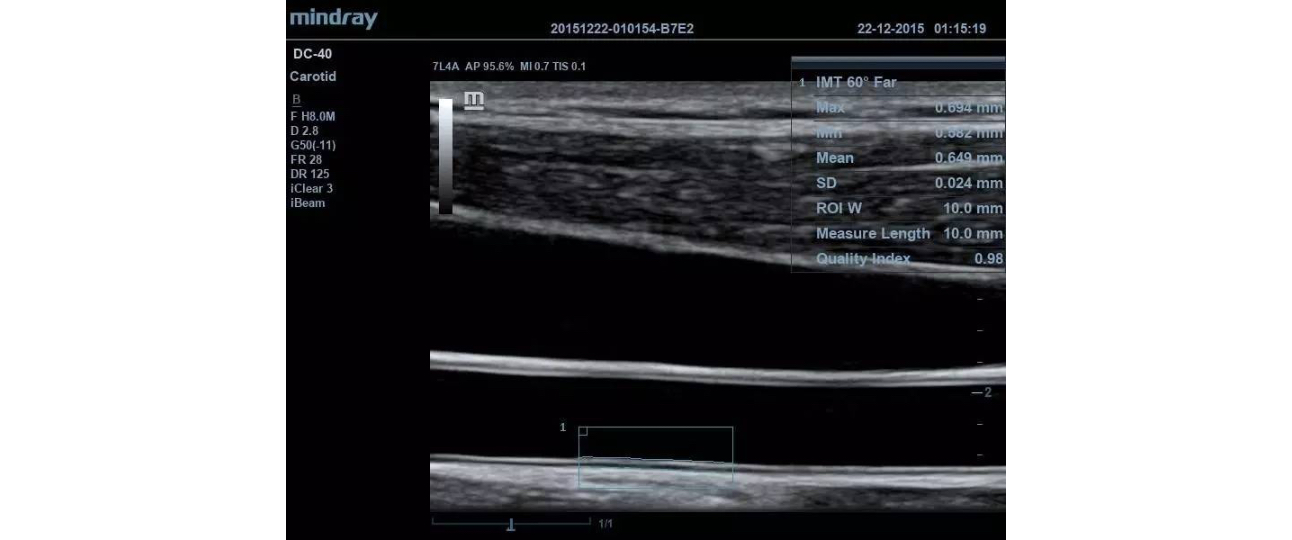

The DC-40 delivers a range of tools that maximize diagnostic accuracy. Covering General Imaging, OB/GYN and Cardiology, the DC-40 provides complete solutions including Natural Touch Elastography, advanced 4D imaging with iLive & iPage, Auto IMT, UWN Contrast Imaging, TDI & TDI QA, Free Xros M and FreeXros CM.

IMT of Common Carotid Artery